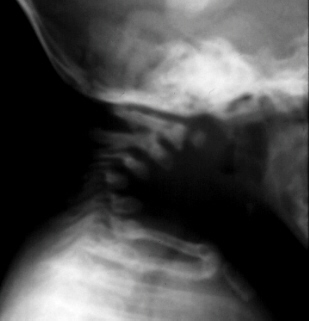

Diastrophic dwarfs do not present atlo-axial instability or foramen

magnum stenosis. In some cases their C-spine develops progressive

kyphosis secondary to wedging of the lower cervical vertebrae. Progression

of this deformity can lead to neurologic deficits and death unless the

patient undergoes posterior or anterior and posterior spinal fusion.

- Spine: generally the vertebral bodies are normal before the development

of spinal deformities. As previously mentioned, cleft laminae are common.

Deformities in C-spine vertebrae.

Cervical kyphosis with C3-C4 deformity and instability since first year

of life.

No neurologic involvement. Several MRIs (91-93) have shown no spinal cord

compression despite a somehow worsening of radiographs.